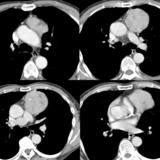

Case 8c Thymoma CT

Date: 03/27/2009

Views: 15480